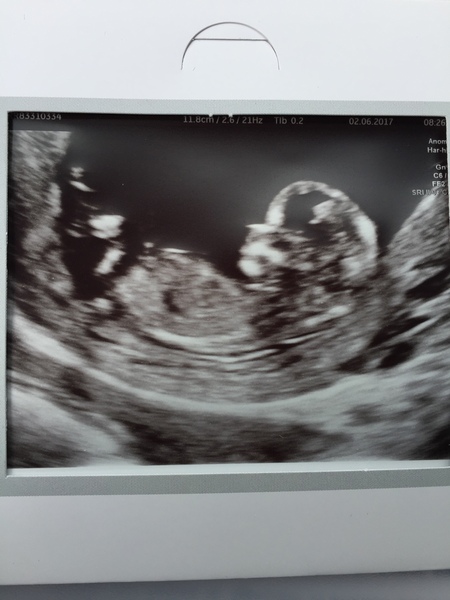

It's my last day at work today before 2 weeks off - yeay! Not going anywhere other than a quick hop to Jersey this weekend to see friends, as we have lots of plans with people visiting us and making over the garden, but have our scan half way through so something to look forward to